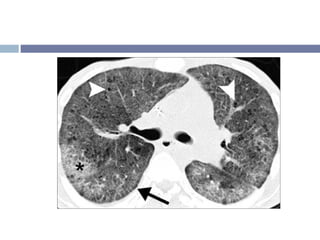

TCAR Quistes pequeños, redondos (2-10 mm). Comparten paredes gruesas. Múltiples capas en la región subpleural. Bronquiectasias de tracción y bronquioloectasias. Opacidades reticulares subpleurales Gradiente ápico-basal

Distribución Bilateral y en parches Periférico y subpleural, más prominente en los segmentos posteriores Predominantemente basal..

Otros signos radiológicos Patrón reticular irregular inter e intralobular Opacidades en vidrio despulido asociado a bronquiolectasias. Crecimiento de GL mediastinales (50-90%), más frecuente en las formas extensas.